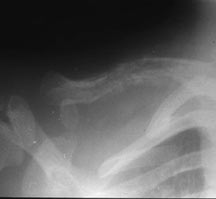

- May arise from any bone and any site within a bone (epiphyseal, metaphyseal, diaphyseal)

- Radiographically variable appearance: may appear benign (geographic) or malignant (permeative or moth eaten)

- Any bone but 90% have skull involvement

- Flat Bones (most common—70%)

- Skull

Radiographic Presentation